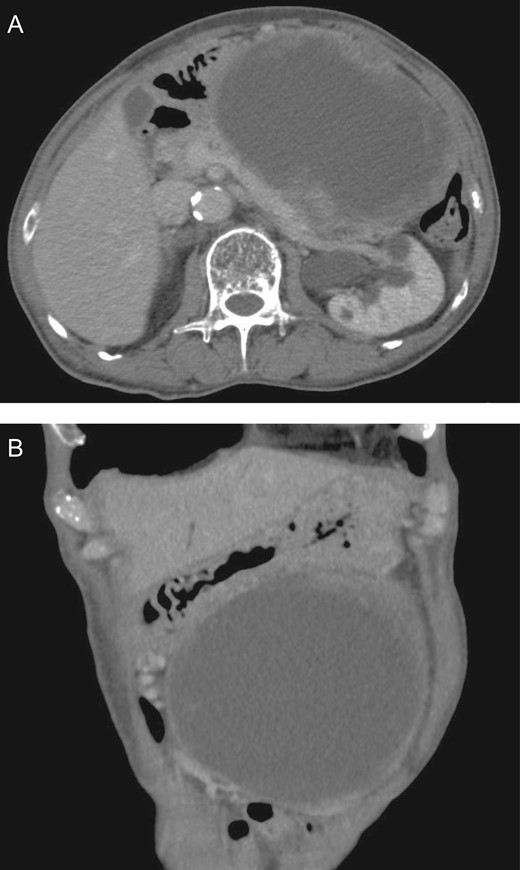

A 64-year-old Japanese man consulted our hospital due to an abdominal mass that had persisted for 1 month. He also had a history of appetite and weight loss. He had a past history of a duodenal ulcer and resection of the left adrenal gland due to primary aldosteronism. He had hypertension and paroxysmal atrial fibrillation, as well as rheumatoid arthritis. Computed tomography (CT) revealed a 180-mm tumor in the posterior region of the gastric body (Fig. 1A and B). The tumor consisted of solid and cystic parts. The primary tumor site was unclear on imaging. There was no significant lesion observed in the mucosa of the upper and lower digestive tracts on endoscopic examination.

Image of abdominal CT Scan. CT scan revealed a tumor 180 mm in diameter in the region posterior to the gastric body. There was a large cyst in the tumor. Horizontal (A) and coronal (B) sections of the tumor are shown.